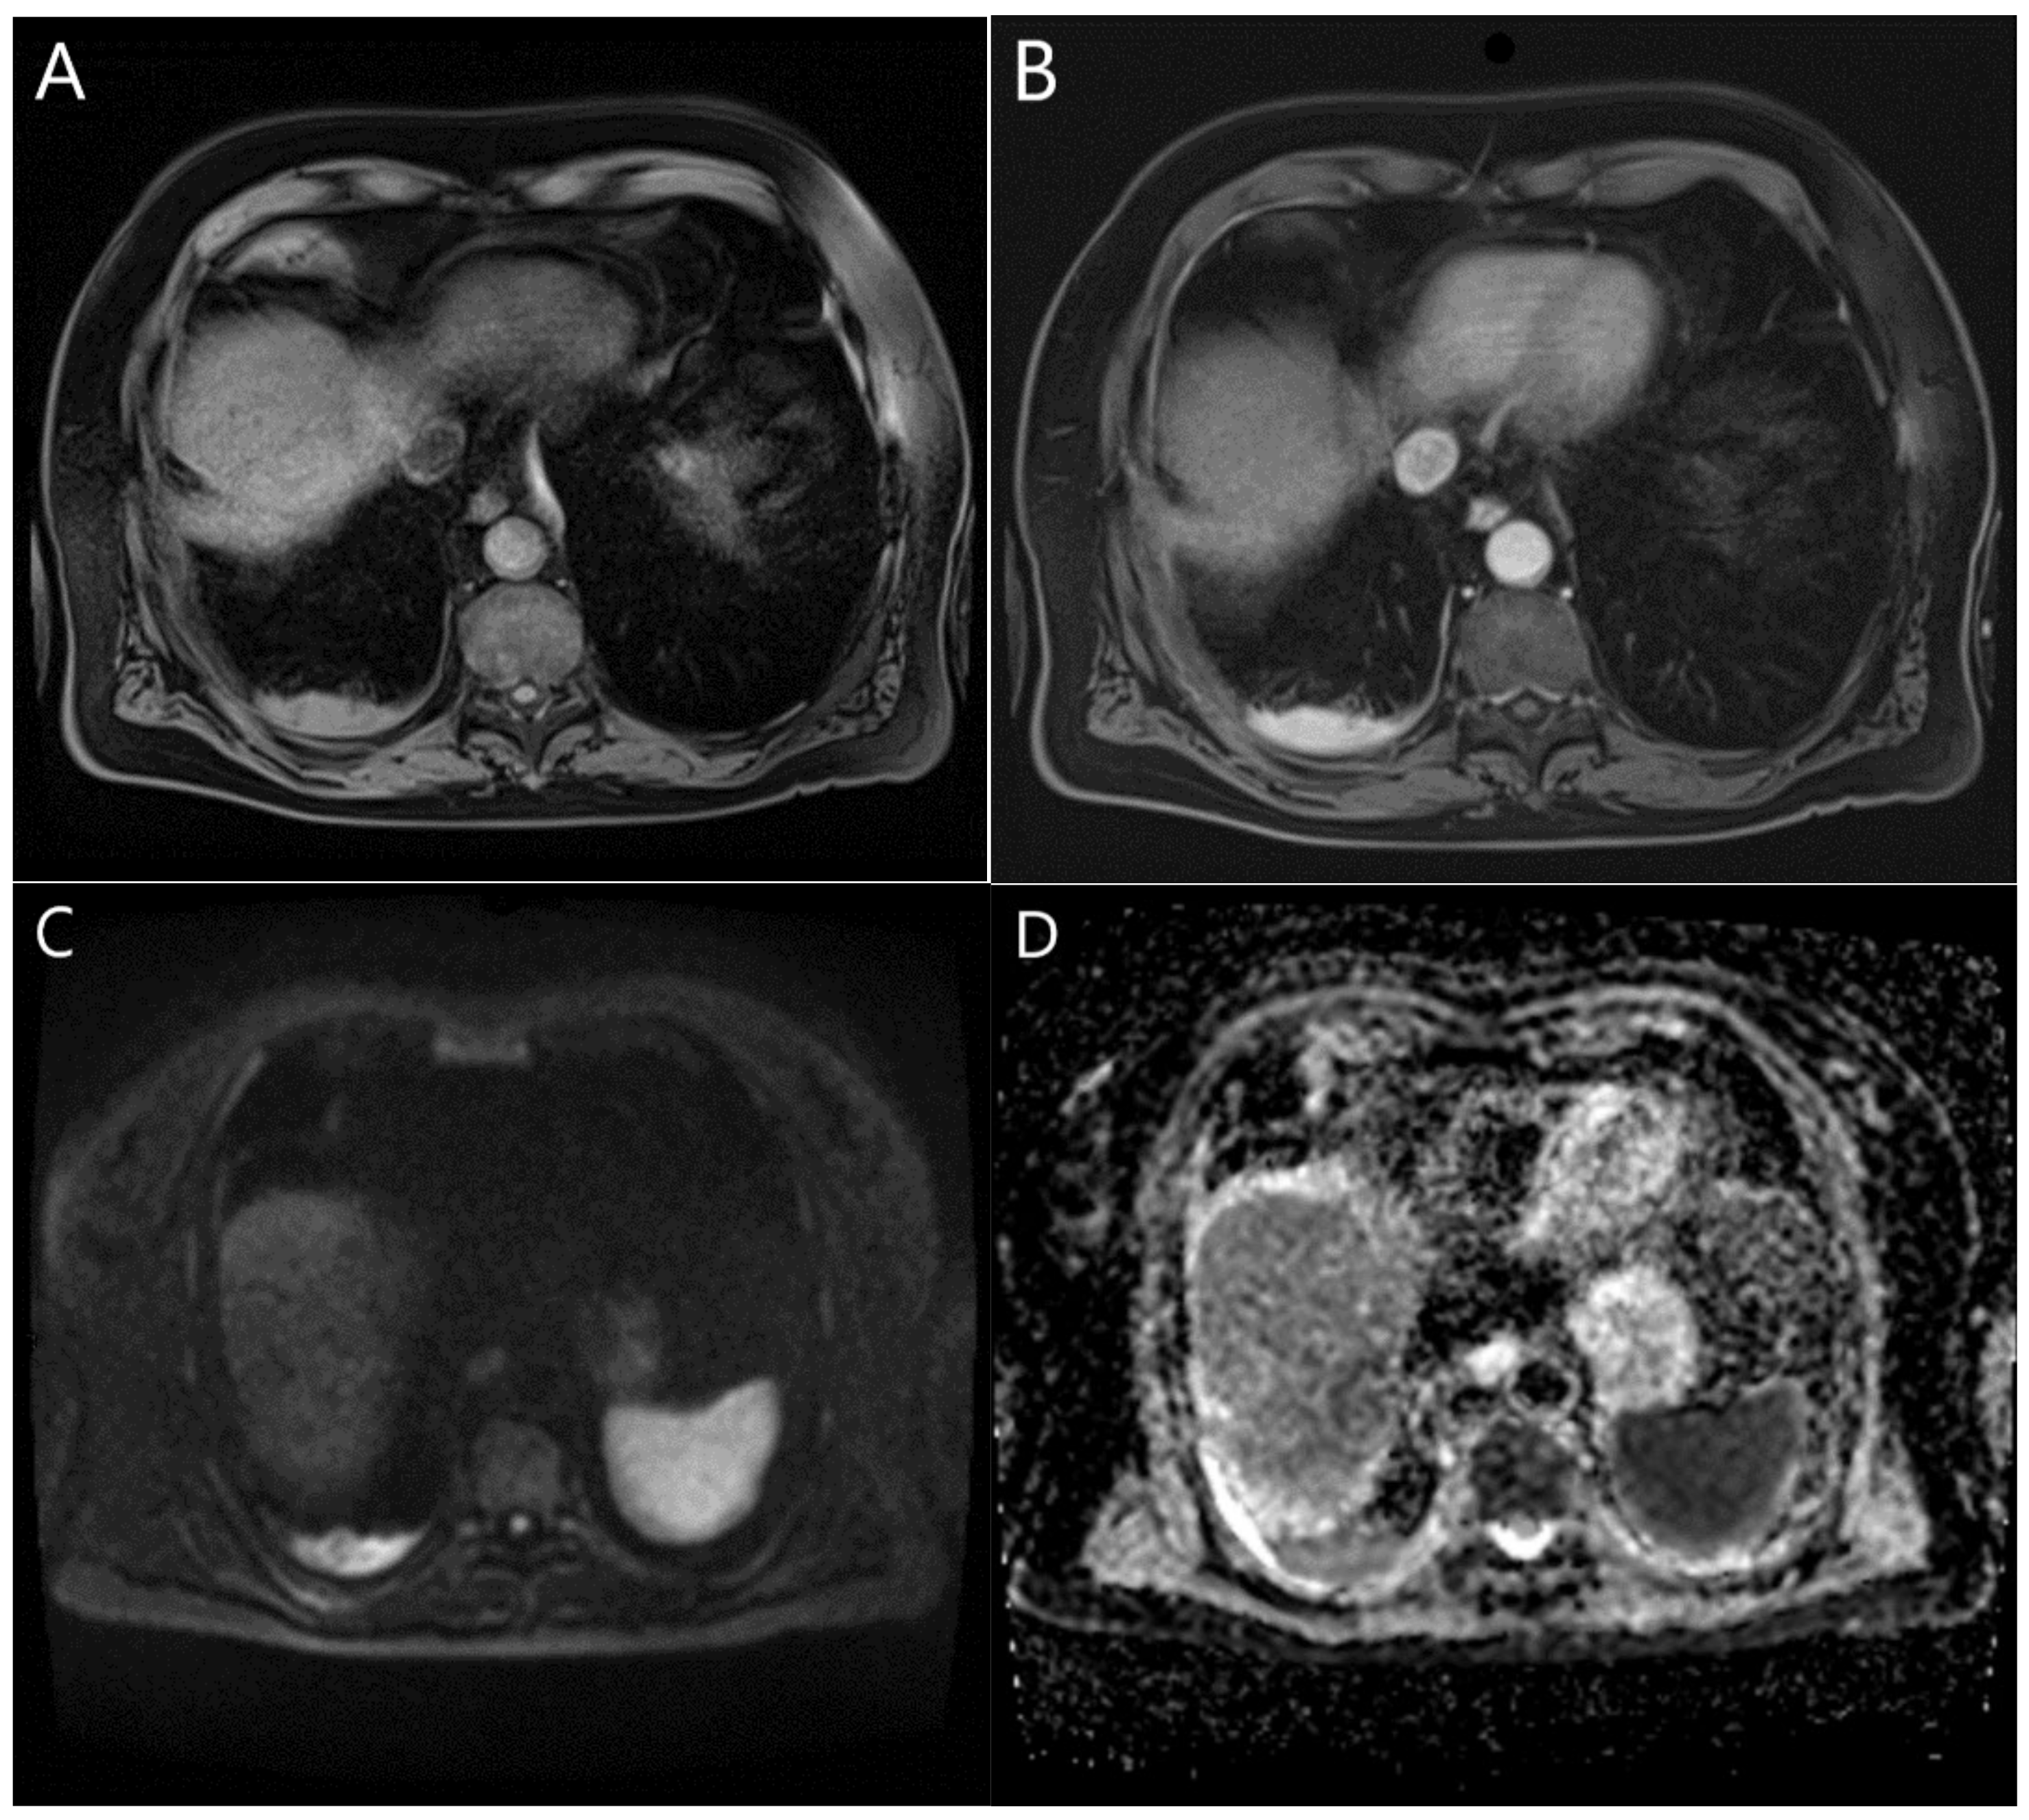

| MPM | Pleural thickening, nodules, masses—isointense/mildly hyperintense in relation to the chest wall muscle * [1,2,3,13,75,76,82,84,85,104]. Pleural effusions—low signal intensity [10,92]. | Moderately enhanced signal after gadolinium administration [75,76]. Pleural thickening—diffusely enhanced [92]. | Pleural thickening, nodules, masses—moderately hyperintense in relation to the chest wall muscle [1,2,3,13,75,76,77,84,85,104]. Unilateral pleural effusion—focal high signal intensity [2,9,82]. Pleural fluid—focal hyperintense areas [13]. Pleural effusions—high signal intensity [10,75,92]. |